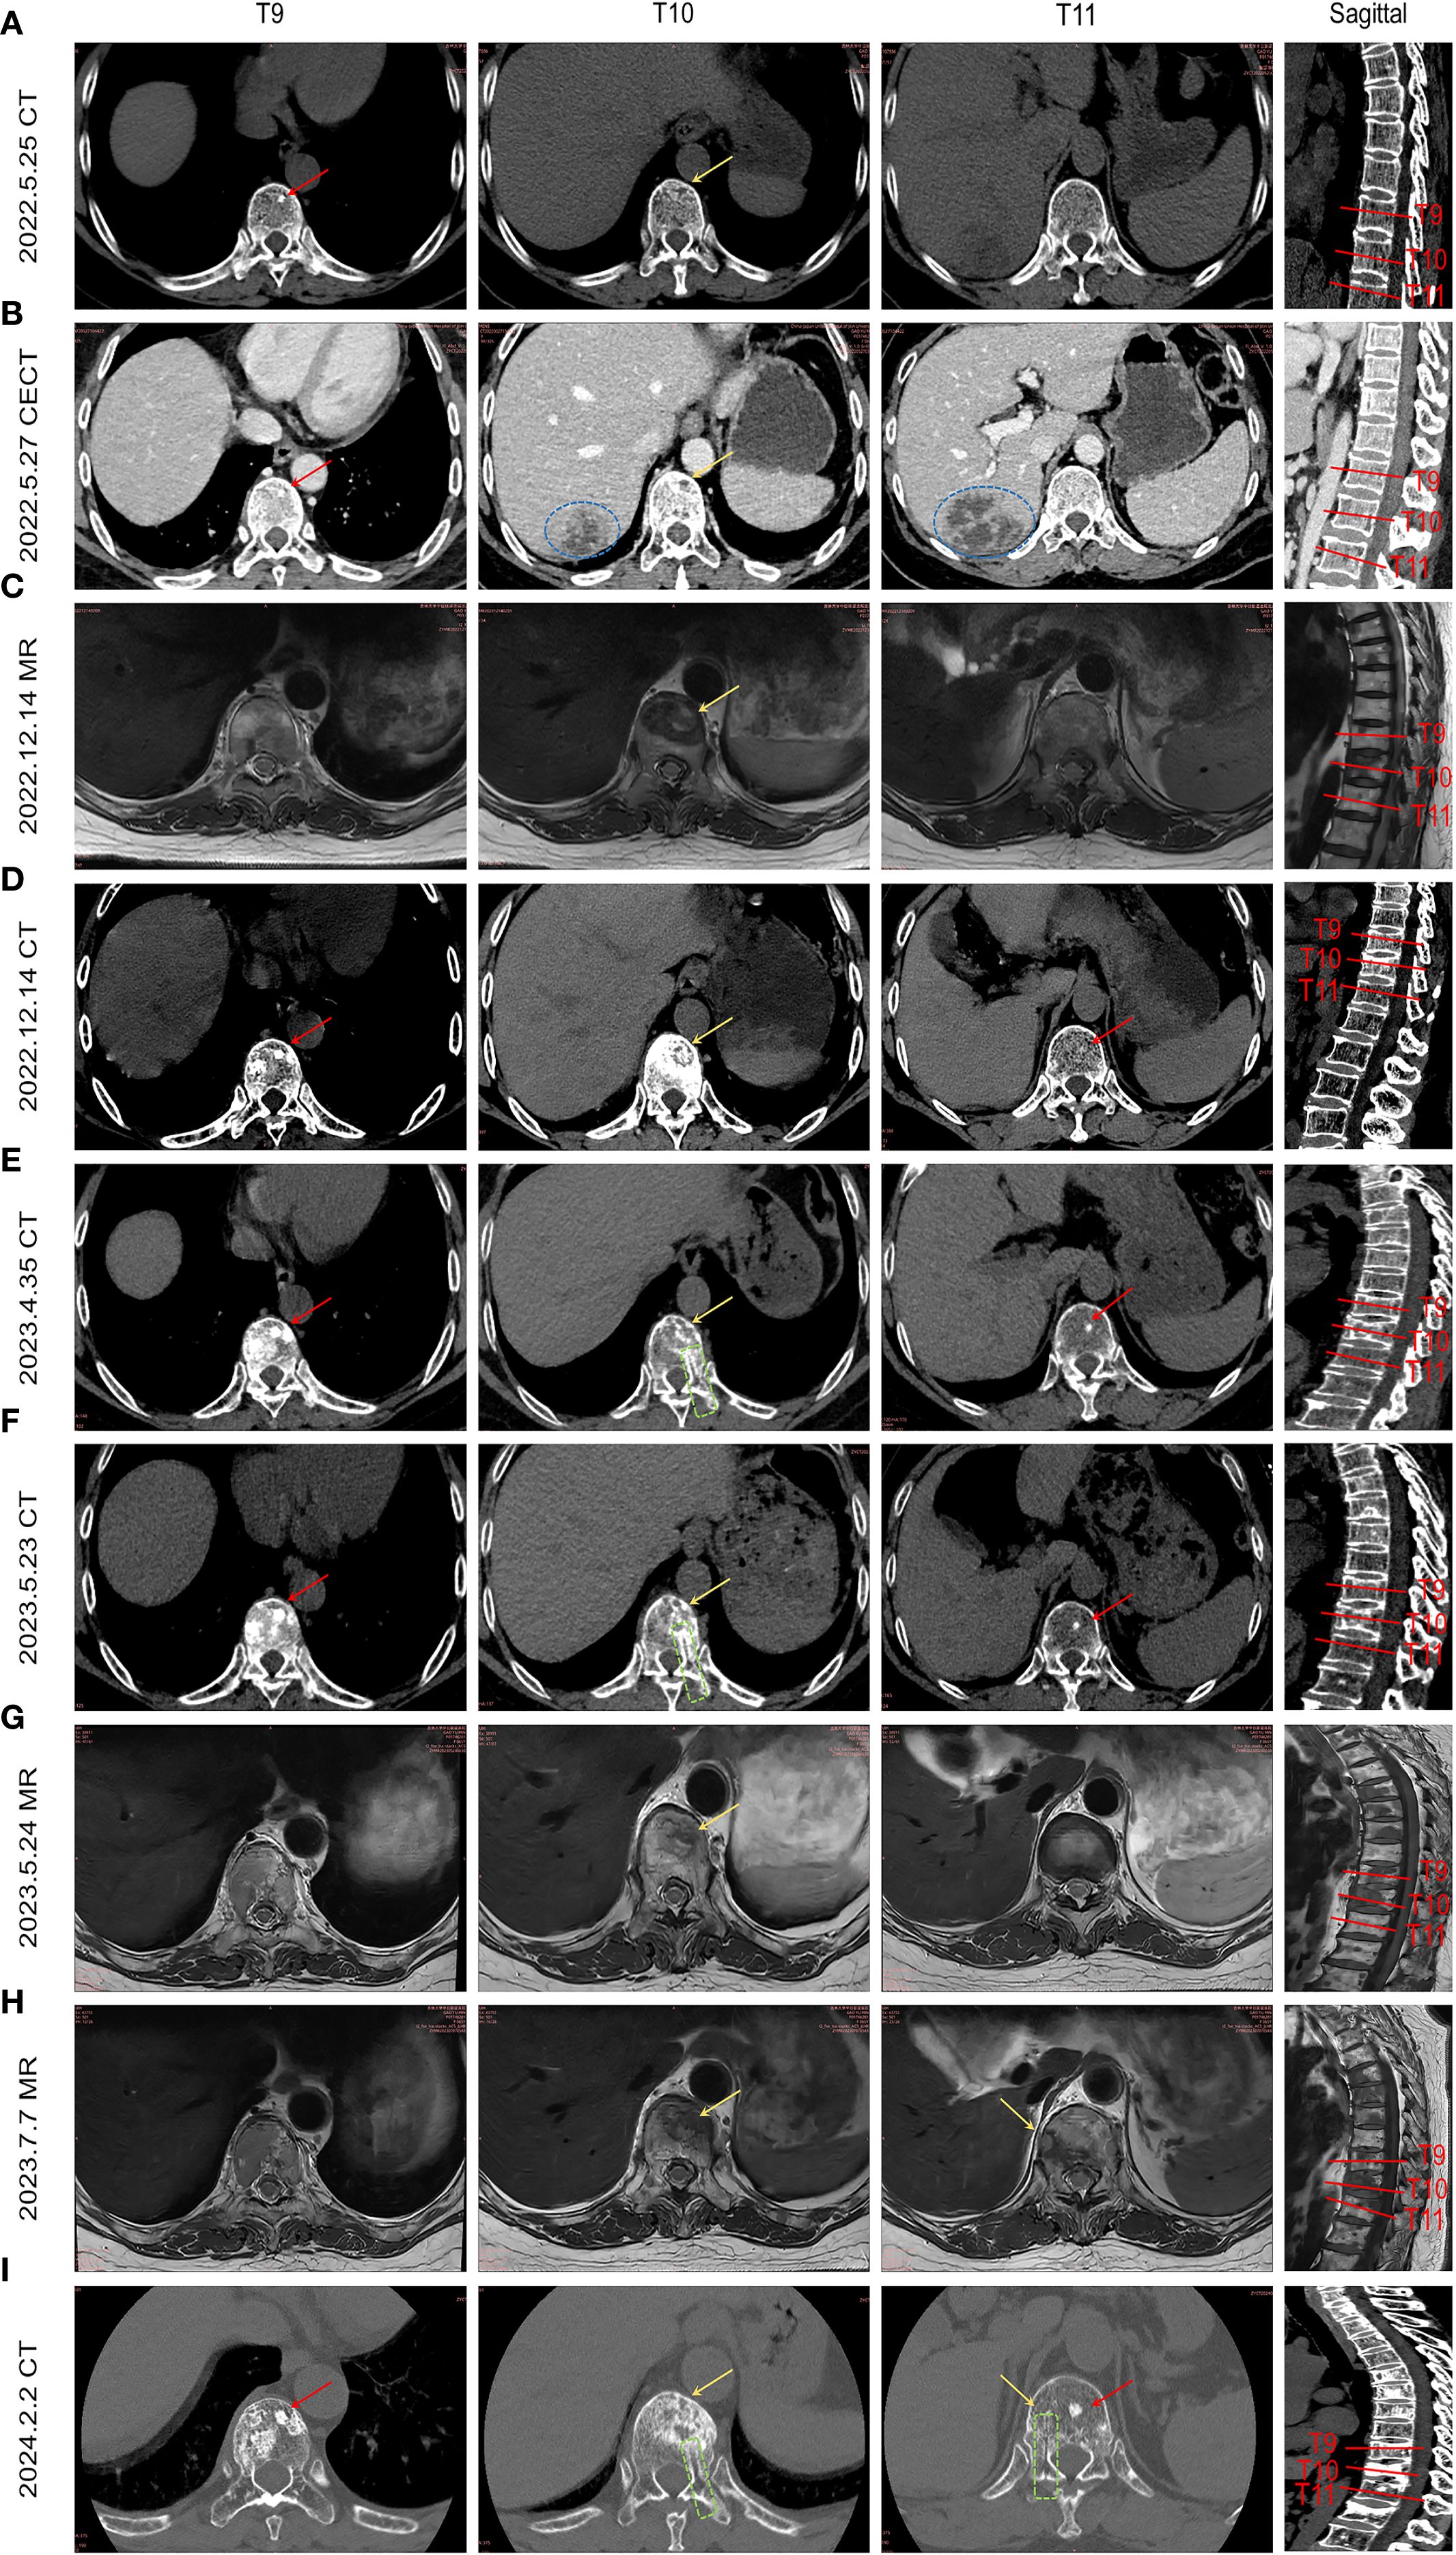

Serial imaging during the patient’s liver abscess hospitalization (initial abdominal CT: Figure 2A; follow-up CECT: Figure 2B) revealed incidental T9 vertebral body sclerosis (Red Arrow) and subtle T10 anterior margin moth-eaten destruction (Yellow Arrow), with T11 appearing unremarkable. These early metastatic features were only recognized retrospectively. Subsequent MRI during back pain episodes confirmed progressive T10 destruction (Figure 2C). Eight months post-metastasis, thoracic CT (Figure 2D) demonstrated T9 osteoblastic progression, T10 osteolysis with peripheral sclerosis, and new T11 sclerotic lesions. Follow-up CT (Figures 2E, F) showed expanding osteoblastic lesions at T9/T11 (Red Arrows), advancing T10 osteolysis (Yellow Arrows), and a visible biopsy tract (Green box). Concurrent MRI (Figures 2G, H) revealed T10 vertebral collapse and T11 involvement. Post-endocrine therapy imaging (Figure 2I) documented stabilized T9/T11 lesions, regressing T10 osteolysis, no new fractures, and persistent biopsy changes, demonstrating therapeutic response. This progression highlights breast cancer metastases’ heterogeneous radiographic presentation (osteolytic/osteoblastic/mixed), their subtle early imaging profile, and distinct growth patterns: osteoblastic foci exhibiting rapid vertebral dissemination within 6–8 months versus typically localized osteolytic lesions (10).

Medical imaging sequence showing multiple cross-sectional CT and MR scans of thoracic vertebrae T9 to T11 in axial and sagittal views. Each row represents different dates ranging from 2022 to 2024, with arrows indicating specific areas of focus on the vertebrae. Red and yellow markers highlight potential abnormalities or areas of interest, with some scans annotated in blue or green. The sagittal views on the right provide a complete side view of the thoracic spine segment, with vertebrae labeled.

Figure 2. illustrates the temporal evolution of spinal metastasis in the patient. By integrating abdominal CT scans obtained during hospitalization for liver abscess and collating prior MRI/CT images, the imaging progression of breast cancer spinal metastases from onset to final outcome is presented sequentially. (A) Abdominal CT during liver abscess hospitalization shows a high-density shadow in the T9 vertebral body (red arrow) and worm-eaten changes at the anterior margin of T10 (yellow arrow). (B) Contrast-enhanced abdominal CT highlights the liver abscess (blue circle), T9 high-density shadow, and more pronounced worm-eaten changes at T10 anterior margin (yellow arrow). (C) Incidental MRI for low back pain reveals a metastatic lesion at T10 anterior margin (yellow arrow) and mixed signal intensity changes in T9. (D) Thoracic CT after 8 months shows multiple osteoblastic changes in T9 (red arrow), resorptive changes at T10 anterior margin, osteoblastic rim around osteolytic lesions, and new high-density shadows in T11. (E, F) Lesions progress with expanding osteoblastic foci in T9 and T11 (red arrows), enlarged worm-eaten changes at T10 anterior margin (yellow arrow), and a visible biopsy tract (green box). (G, H) Sagittal views show expanded T10 anterior lesions with compression fracture, metastatic involvement at T11 edge. (I) Eight-month follow-up thoracic CT after endocrine therapy demonstrates stabilized T9/T11 lesions (red arrows), improved T11 anterior worm-eaten changes (yellow arrow), no new compression fractures, and persistent biopsy tract (green box).